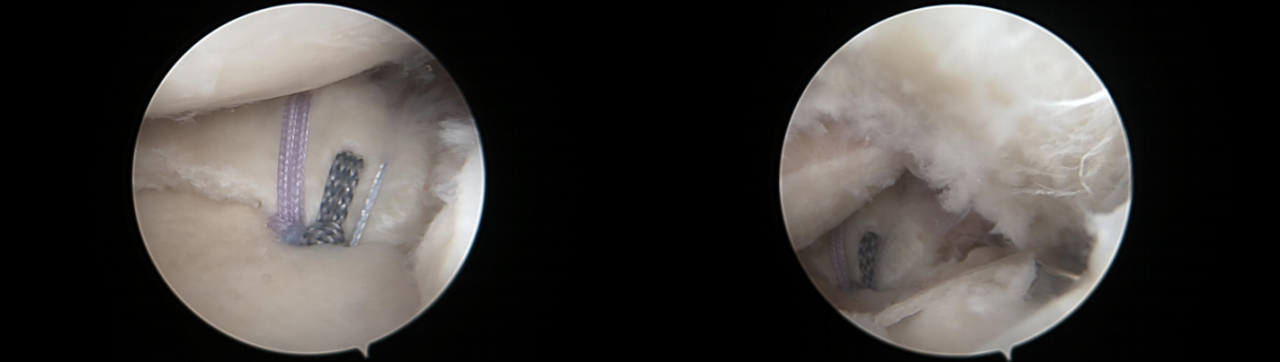

镜下双袢联合高强线“三重固定”

步骤2:插入两条PDS线并引入高强线,分别并将其穿过后交叉韧带,以形成初始的吊带环。

第三步:双套环高强线复位骨折块,并穿入固定微孔钛板。

步骤4:将一根高强度缝合线穿过骨隧道,并牢牢收紧,以准确复位骨折段。

第五步:拉紧双环以稳定骨折部位,并抓住两条牵引缝线。

步骤6:紧固牵引缝线以防止固定环滑脱。